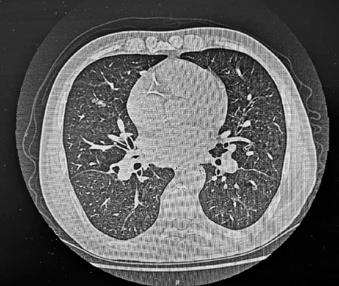

Manifestări cutanate în diabetul zaharat

Diabetul zaharat, o afecțiune metabolică complexă, cauzează hiperglicemie cronică și are un impact semnificativ asupra sănătății publice, generând costuri estimate la 412,9 miliarde de dolari în SUA în 2022. Acesta are două forme principale: tip 1 și tip 2, fiecare având implicații economice și sociale considerabile. Manifestările cutanate asociate cu diabetul, cum ar fi acanthosis nigricans, necrobioza lipoidă, bullosis diabeticorum, dermopatia diabetică, xantomatoza eruptivă și granulomul annulare, pot indica severitatea afecțiunii și complicațiile sale. Acanthosis nigricans este corelată cu hiperinsulinemia și apare adesea în zonele axilare și pliuri, în timp ce necrobioza lipoidă afectează în special membrele inferioare. Bullosis diabeticorum se manifestă prin buloase spontane fără inflamație, iar dermopatia diabetică se reflectă prin leziuni hiperpigmentate. Infecțiile cutanate, frecvente la pacienții diabetici, sunt agravate de controlul glicemic deficitar, incluzând atât infecții bacteriene cât și fungice. Reacțiile de hipersensibilitate la tratamentele antidiabetice punctează nevoia unei abordări multidisciplinare în managementul diabeticilor. Această revizuire evidențiază necesitatea examinării dermatologice în diagnosticul și monitorizarea diabetului. Cercetările ulterioare ar trebui să vizeze elucidarea mecanismelor patogenetice și dezvoltarea de strategii terapeutice personalizate pentru optimizarea controlului glicemic și pentru prevenirea complicațiilor dermatologice.

vând în vedere creșterea alarmantă a prevalenței diabetului și implicațiile socio-economice, această patologie devine o prioritate majoră pentru sănătatea publică. Este esențială implementarea unor strategii integrate care să vizeze prevenția primară, diagnosticarea timpurie și intervențiile terapeutice moderne, măsuri esențiale pentru îmbunătățirea managementului metabolic și reducerea riscului de complicații pe termen lung [3]

Examinarea dermatologică prezintă un rol important în identificarea precoce a diabetului zaharat și a prediabetului, având în vedere impactul sistemic al

acestei afecțiuni care poate determina sau debuta cu o serie de manifestări cutanate [4]. Un studiu observațional prospectiv desfășurat într-o clinică de diabetologie a demonstrat faptul că leziunile cutanate au fost prezente la peste 98% dintre pacienții cu diabet zaharat de tip 2 și la 34% dintre cei cu diabet zaharat de tip 1. Deși 98% dintre pacienții cu DZ cu o durată de peste 5 ani au prezentat manifestări cutanate, afectarea cutanată a fost totuși regăsită și la aproximativ 80% dintre pacienții diagnosticați cu DZ de mai puțin de 5 ani [5]

Modificările metabolice apărute pe parcursul evoluției diabetului favorizează dezvoltarea unor dermatoze caracteristice, cum ar fi acanthosis nigricans, necrobiosis lipoidica diabeticorum, bullosis diabeticorum, xantomatoza eruptivă și dermopatia diabetică [4] .